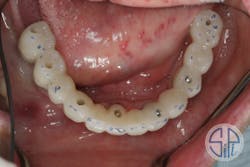

A full-arch restoration on transmucosal abutments was planned. A rigid resin pattern, open-tray, implant level impression was taken (figure 1). The laboratory provided the dentist with straight, transmucosal abutments (figure 2) and a verification jig that was used to verify occlusion, phonetics, and esthetics (figure 3).

Following this verification step, a zirconia restoration was fabricated and delivered (figure 4). While screwing the restoration into place, a cracking sound was heard. The restoration had fractured lingually to the access hole of dental implant No. 27 (figure 5).

Figure 4: Newly delivered zirconia restoration